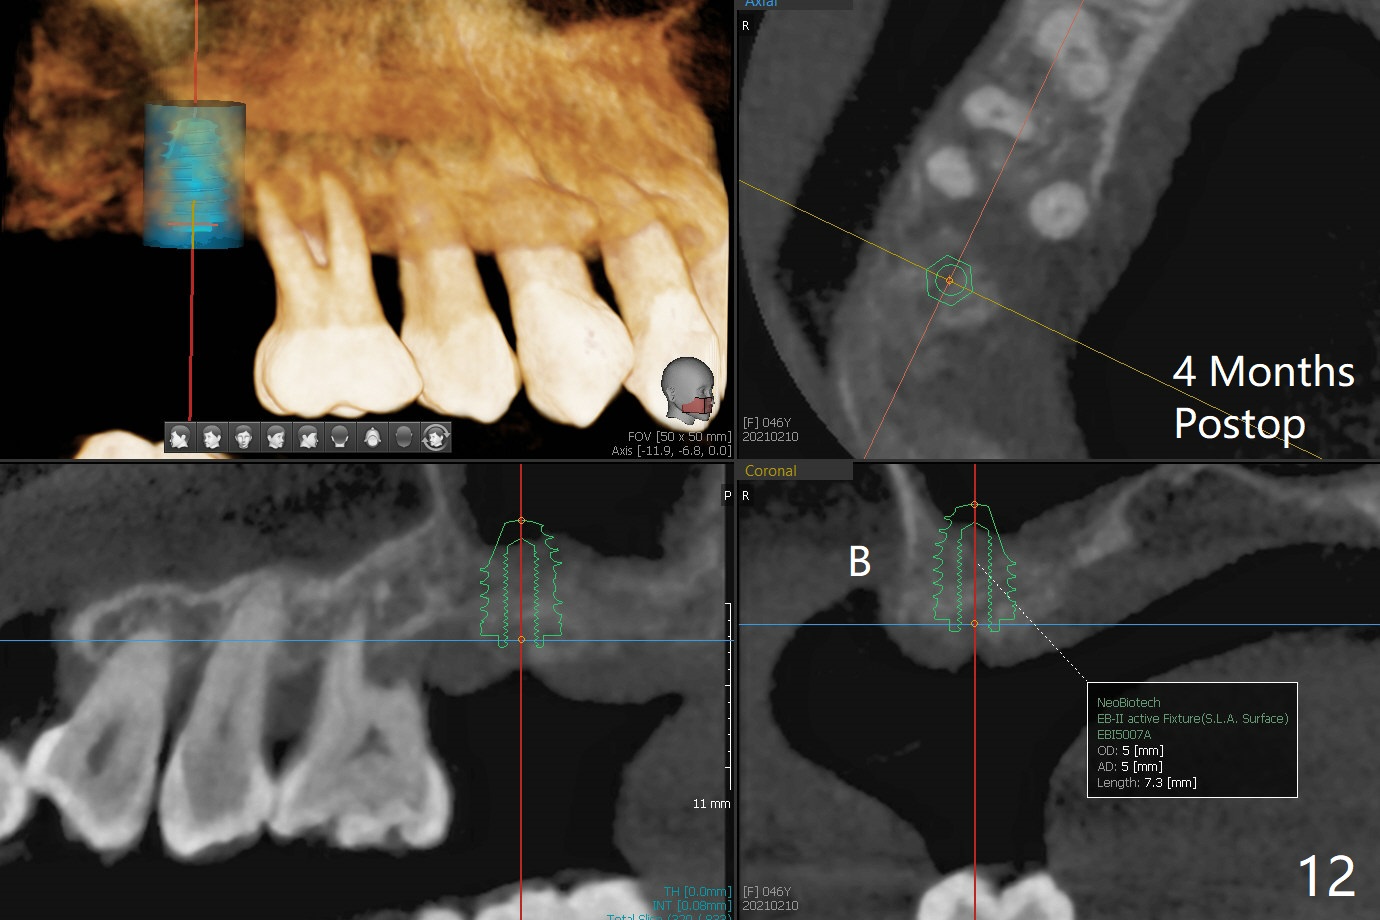

尽管右上第一,二磨牙骨质吸收严重,为了保持牙乳头,先拔除有症状第二磨牙,但是后者牙槽窝与第一磨牙之间好像没有软组织(图二:*),所以骨粉(图一,二:7)无法从前者推入后者(图二(下一个成功病例))。骨粉表面放置6个月吸收膜(GEM Cap(图三::C)),使用牙周胶水固定,而且装置牙齿空间维持器(图二:S)和牙周敷料强化固位。牙齿拔除证实腭侧牙槽窝(图四:P)上颌窦底板穿孔(^;但是没有漏气)。虽然病人已经服用Amoxicillin一周以及Z Pack(两颗,术前),为了防止感染介入上颌窦,穿孔冠部放置胶原塞(图五:黄色),然后放置骨粉(红色)。后者仿佛增加骨质高度不少(图二)。如果不够,以后再做提升。多亏间隙保持器,牙周敷料术后4天没有松动迹象(图六)。术后三周敷料颊侧有些破裂(图七),而舌侧完整(图八)。嘱咐病人正常刷牙和水牙线,让敷料自行脱落。其实术后六周敷料仍在原位,不可吸收膜粘附于敷料,两者一起去除,伤口愈合(图九),骨粉好像没有损失(图十)骨高度减少。术后4个月骨质高度继续减少(图十一)。植骨后骨质高度还与邻牙一致,密度低,可植入5x7.3毫米植体(图十二)。